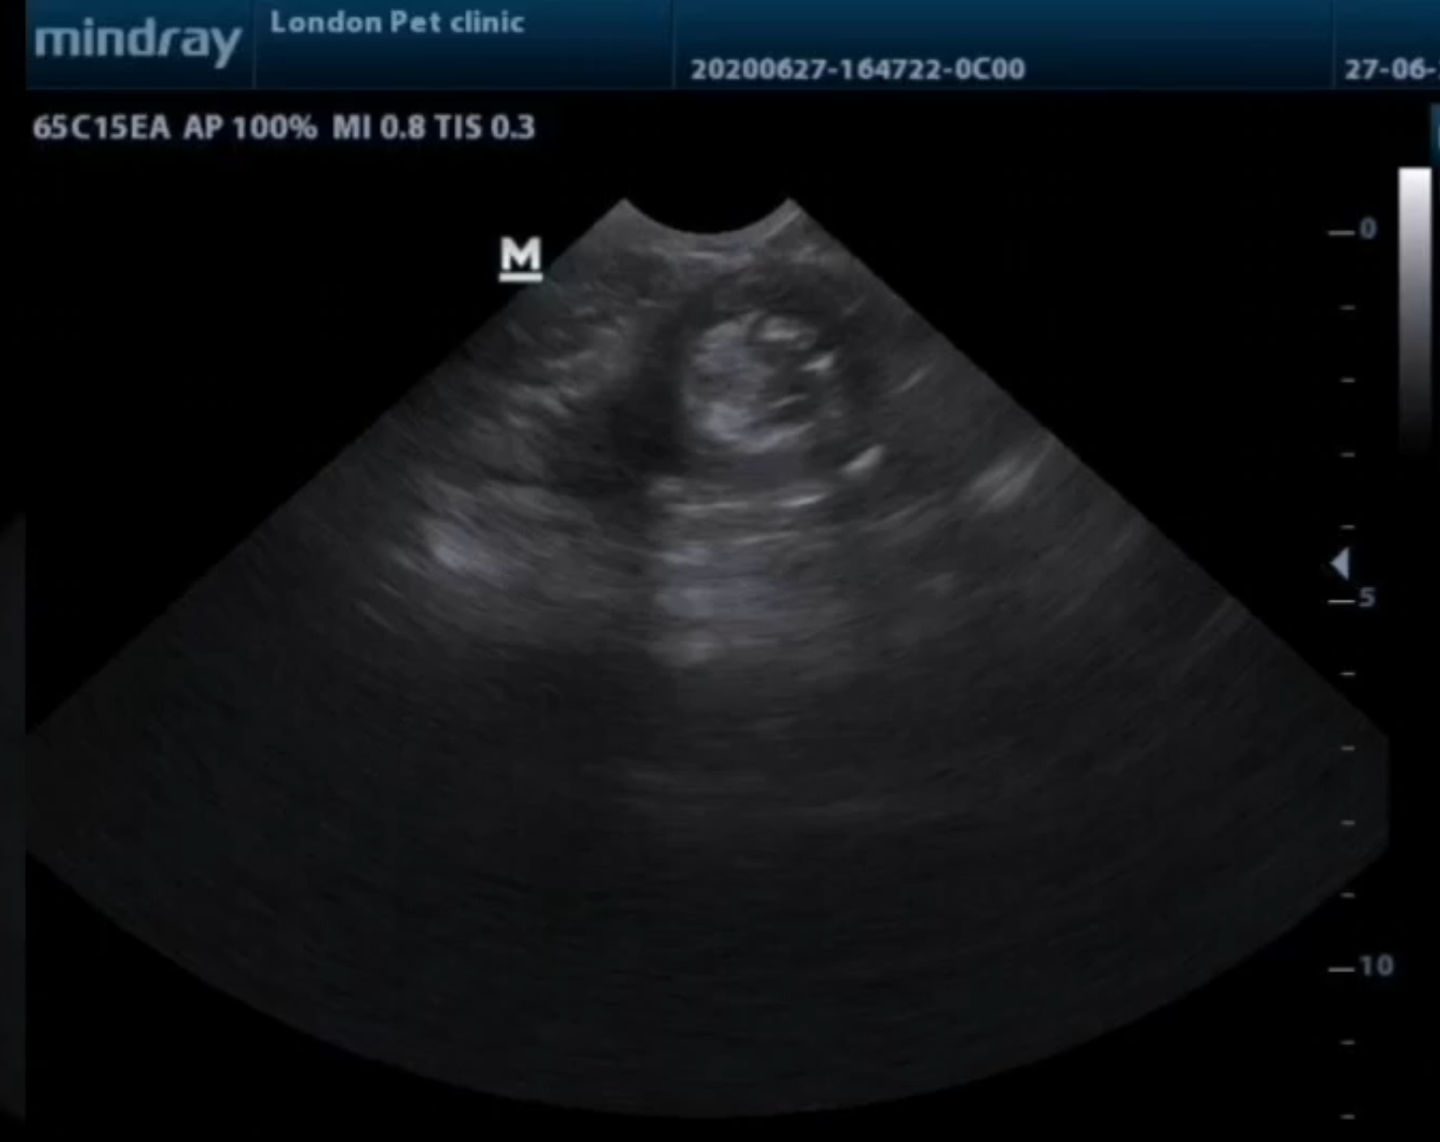

Abdominal ultrasonography revealed a characteristic “target sign” confirming intestinal intussusception

characteristic “target sign” of the intussusception